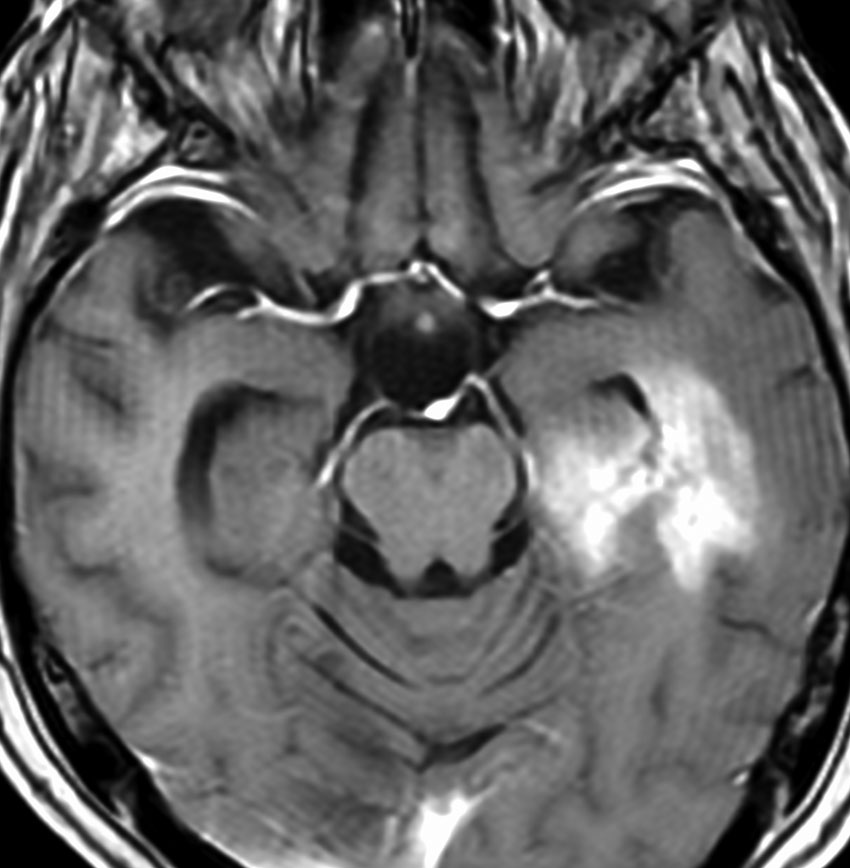

ゆっくり進行する軽い右麻痺で発症した50歳くらいの患者さんです。脳梗塞や脱髄疾患を疑われていました。左頭頂部皮質下から脳梁,内包,中脳大脳脚まで非常に広範囲に浸潤しています。single cell infiltrationという浸潤形態を想像させます。右下はT!ガドリニウム造影で,この部分だけが増強所見があります。

おそらく今後は,diffuse hemispheric glioma WHO grade 4と診断されます。

軽度の異型性を認め,細胞密度が高く核分裂が目立ち,Ki-67 (MIB)染色率は20%に達しました。1p/19q欠失はなくMGMTメチレーションもありませんでした。IDH変異は調べていない年代の例で不明です。病理組織診断でanaplastic astrocytomaとされました。治療は,全脳に近い照射野となるので50Gy/25分割が限界でした。TMZを併用しています。